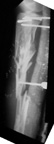

Tibia Fx ForumCase 1

I would appreciate treatment suggestions.My patient is a 30 year old with a very comminuted tibia fracture 6 weeks ago.It was grade 3B open. Initial treatment included irrigation, debridementClick images to enlarge.

and a hybrid external fixator including femur, tibia and foot. Screwswere placed in the plateau and plafond and a free flap plus STSG. Theskin is ok but atrophic. The femoral pins were removed and knee motionstarted at 6 weeks. There is no sign of callus. There is one pin inthe one large fragment of the diaphysis. All the pieces are lined upreasonably well. The XF pins are ok. Suggestions? Thank you.